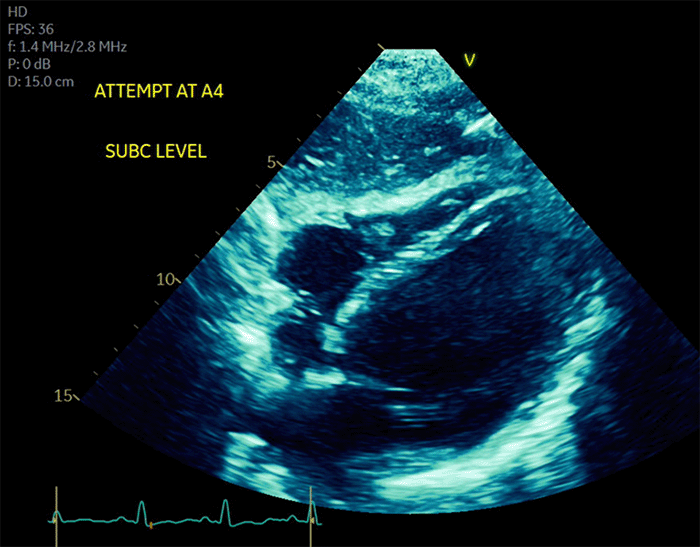

She was promptly re-intubated and emergently transferred from the outpatient surgery center to the Trauma Surgical Intensive Care Unit (TSICU) at our university hospital. Initial resuscitation involved aggressive hemodynamic support, including high-dose vasopressors and inotropes, with norepinephrine initiated up to 0.2 mcg/kg/min and epinephrine up to 0.26 mcg/kg/min. In the TSICU, a transthoracic echocardiogram (TTE) revealed severely reduced left ventricular systolic function, with an estimated ejection fraction (LVEF) of less than 30% (Figure 1). The echocardiogram demonstrated a distinct pattern of mid-chamber hypokinesis with preserved contractility at the base and apex of the left ventricle, characteristic of mid-ventricular Takotsubo cardiomyopathy (TCM). Concurrent electrocardiography showed sinus tachycardia without ST-segment changes or other findings indicative of acute coronary syndrome or myocardial infarction (Figure 2). Her high-sensitivity troponin level was elevated, peaking at 227 ng/L on postoperative day one.

Figure 1. Transthoracic Echocardiogram Demonstrating Mid-Ventricular Dysfunction. Published with Permission

Apical four-chamber view from a transthoracic echocardiogram performed on postoperative day 0